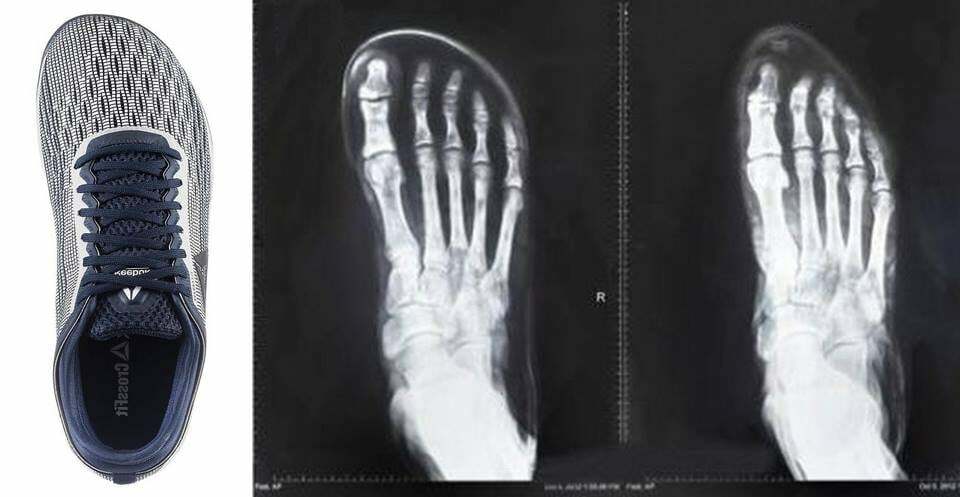

Prends des nano si tu peux, elles sont plus adaptées notamment car plus large devant pour compenser l'absence de drop au talon. En complément je te conseillerais plutôt que courir de travailler ta mobilité, ça te servira sûrement plus ^^ |